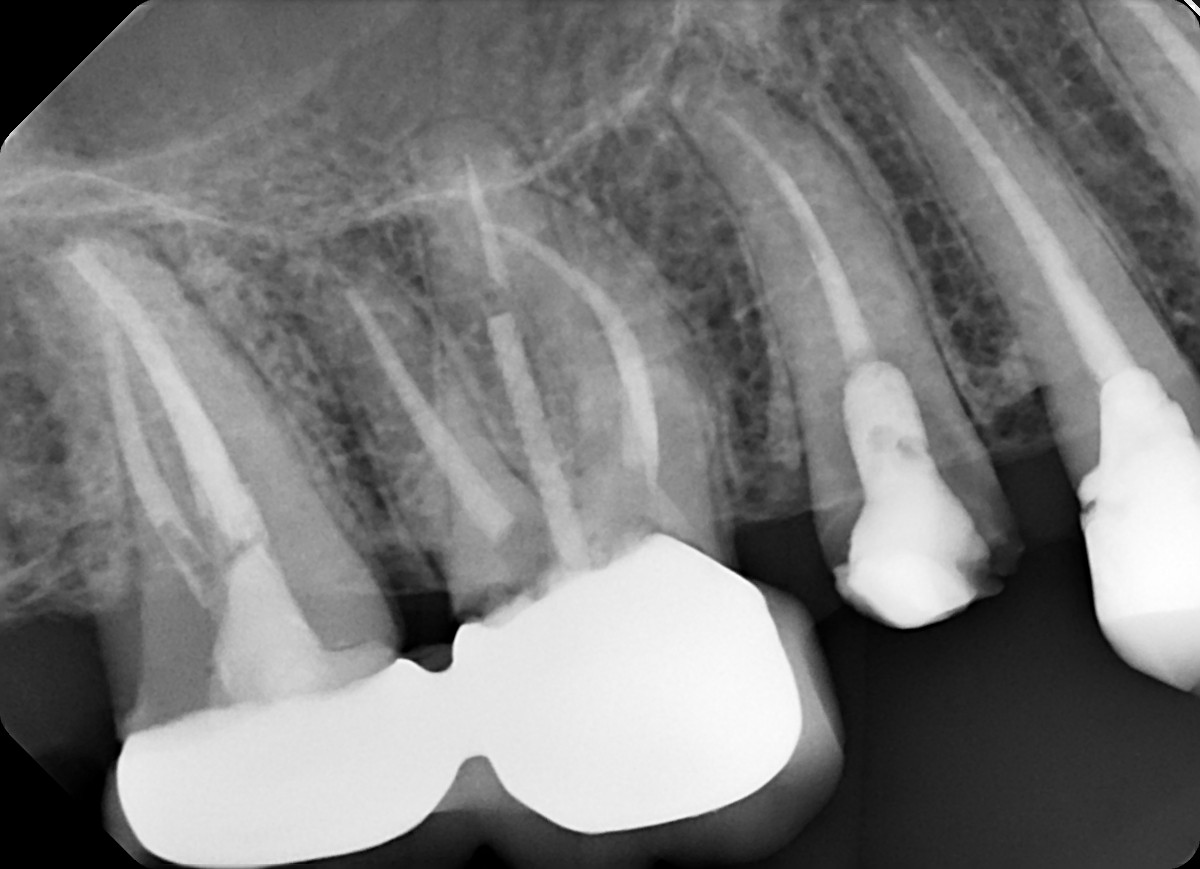

24 / 35

24. On which surface a recurrent caries can be detected?

no recurrent caries can be seen in this X ray